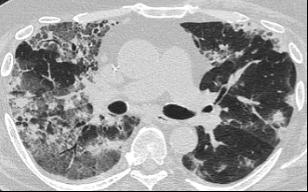

A 58-year-old female with recently diagnosed COVID-19 pneumonia was found to have a dry cough and dyspnoea in the setting of persistent bilateral hilar and mediastinal lymphadenopathy associated with bilateral nodular infiltrates. Of note, she immigrated to the USA from India 10 years prior, with the most recent travel to India 2 years ago. Quantiferon testing upon return to the USA was negative at that time. Workup included bronchoscopy with endobronchial ultrasound revealing non-caseating granulomas with negative stains for acid-fast bacilli (AFB). She was diagnosed with Stage 3 sarcoidosis and initiated on prolonged steroid taper with improvement of symptoms. With taper of steroid dose, however, she developed lymphocyte-predominant exudative effusion with negative cultures, and was reinitiated on a protracted steroid course with rapid symptom resolution. At 4-month follow-up, she had worsening CT findings upon steroid taper, and was started on azathioprine. One month later, she required hospital admission for worsening dyspnoea and fatigue. She was noted to be febrile, tachycardic, and tachypnoeic with worsening

hypoxia. Subsequent CT chest showed progression of bilateral nodular infiltrates with new right upper lobe consolidation and air bronchograms concerning for multifocal pneumonia (Figure 1). Incidentally, she was also noted to have calcified splenic granulomas. She developed rapid clinical deterioration, ultimately requiring mechanical ventilation, pressor support, and continuous renal replacement therapy. Repeat bronchoscopy revealed diffuse alveolar haemorrhage with multiple AFB smears positive for Mycobacterium tuberculosis. She was immediately initiated on quadruple therapy, but unfortunately, despite treatment, developed refractory shock and passed away 2 weeks after initial presentation.

A) Initial adenopathy with peripheral patchy ground glass opacities in the right lung following COVID-19 pneumonia. B) Persistent bulky adenopathy 1 year after initial presentation. C) Extensive nodularity throughout the right lung with increasing confluent opacities in the right upper lobe and stable mediastinal lymphadenopathy 2 years after initial presentation. D) Tuberculosis superimposed on sarcoidosis with progression of nodular infiltrates, worsening right upper lobe consolidation, and air bronchograms with incidental calcified splenic granulomas (not pictured).

Figure 1: CT progression of patient’s sarcoidosis and tuberculosis.